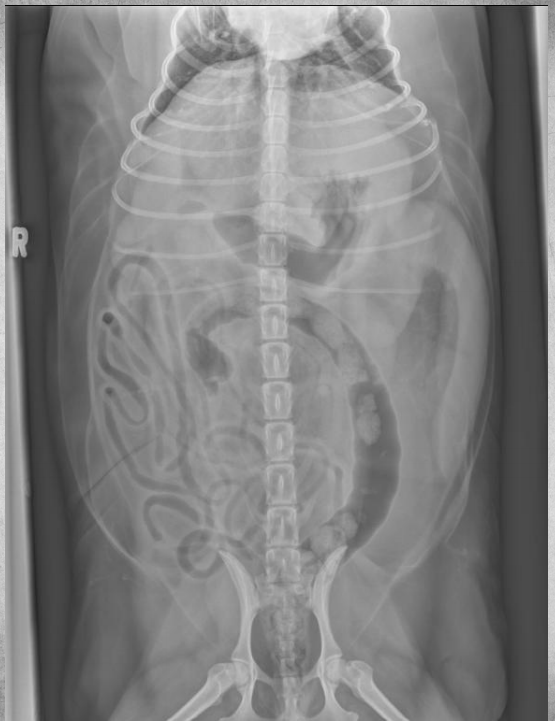

●6 mo female Great Dane

●Vomiting, loss of appetite for 3 days

●Suspected foreign body

● Entire small intestine moderately homogenously fluid filled, teeny bubbles throughout GI tract indicating GI hypomotility.

● Markedly gas-distended intestinal segment in mid-abdomen, reverse C-shaped, most likely normal caecum.

● Diffusedly fluid filled GIT with interspersed gas bubbles is most consistent with functional ileus from severe enteritis.

● No radiographically evident foreign body.

● Dx: Parvoviral enteritis